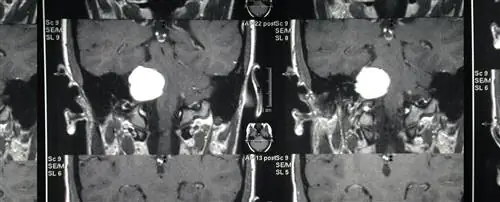

Опухоль головного мозга.

Он умер от злокачественной, безжалостной опухоли головного мозга, когда нашему сыну был год.